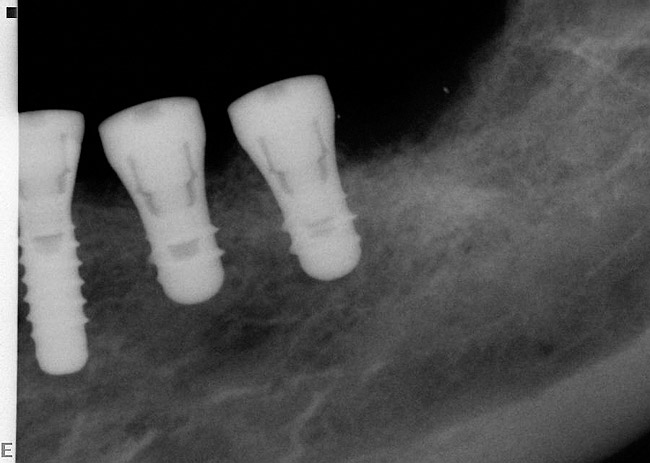

A surgical guide, based on the 3-dimensional implant locations is fabricated for use in conjunction with the selected implant manufacturer's guided surgery instrumentation (Figure 4). Using this template, safe implant positioning in all three dimensions is performed, avoiding trauma to vital anatomic structures respecting the restorative outcome prescribed prior to surgery (Figure 5 and Figure 6). Following 8 weeks of transmucosal healing time, standard restorative therapy is initiated (Figure 7).

Figure 6  Computer-guided implant placement.

Figure 6

Figure 7  Final restoration of computer-guided implants.

Figure 7